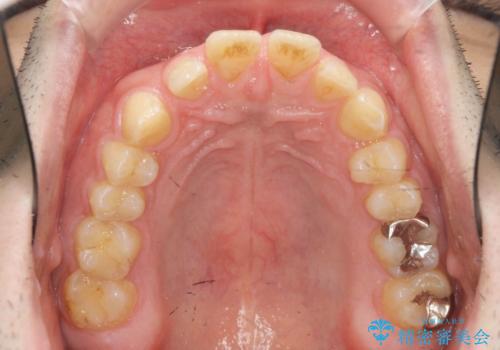

ディープバイトのマウスピース矯正

- 飛び出してしまい、隙間のある前歯をきれいに並べたい、と矯正治療を希望され来院されました。

上顎前歯を後方に引き、隙間を閉じるためには下顎前歯の絶対的な圧下を行い、深い噛み合わせを改善することが必要です。

圧下は歯の動きの中でも難しい動きの一つで時間がかかることが多いです。

前歯でチューイーをしっかり噛み、咬合圧を伝えたことで下顎前歯が圧下し、上顎前歯の隙間を閉じることができました。